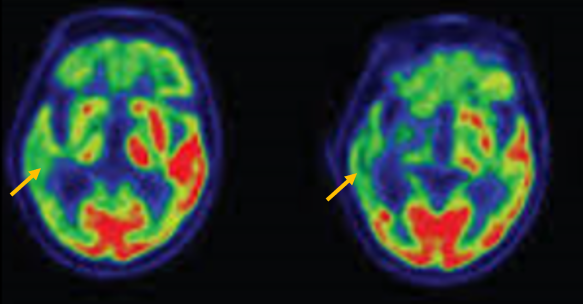

피질 기저핵 변성은 비대칭 증상을 두드러지게 보인다는 점에서 파킨슨병과 비슷합니다. 그러나 파킨슨병과 비교해 보았을 때 양측의 차이가 아주 심하게 나타난다는 특징이 있습니다. 질병 초기에 한쪽 손으로 동작을 하거나 계획된 행동을 하는 기능이 현저하게 떨어집니다. 간단한 손가락 모양도 따라 하지 못하는 현상을 보입니다. 또한 의지와 상관없이 제멋대로 움직이는 통제불능 손이 나타날 수 있습니다. 체위 떨림, 경축, 운동 완만과 같은 파킨슨병에서 볼 수 있는 증상들은 피질 기저핵 변성에서도 관찰될 수 있습니다. 또한 집중력 장애, 수행 장애, 이름 대기나 언어의 유창성이 떨어지는 등 전두엽 및 두정엽과 관련된 인지 장애가 나타납니다. 피질 기저핵 변성은 뇌 자기공명영상(MRI)에서 증상의 반대쪽 전두두정엽의 위축 소견이 특징적으로 나타납니다. 뇌포도당 양전자 단층촬영(PET)에서도 전두엽, 뇌기저핵에 비대칭적인 대사 저하의 소견이 보입니다.

[피질기저핵 변성 환자의 뇌자기공명영상에서 확인되는 비대칭 뇌피질의 소견]

[피질기저핵 변성 환자의 뇌포도당 양전자 단층촬영에서 확인되는 비대칭적인 대사 기능 저하]